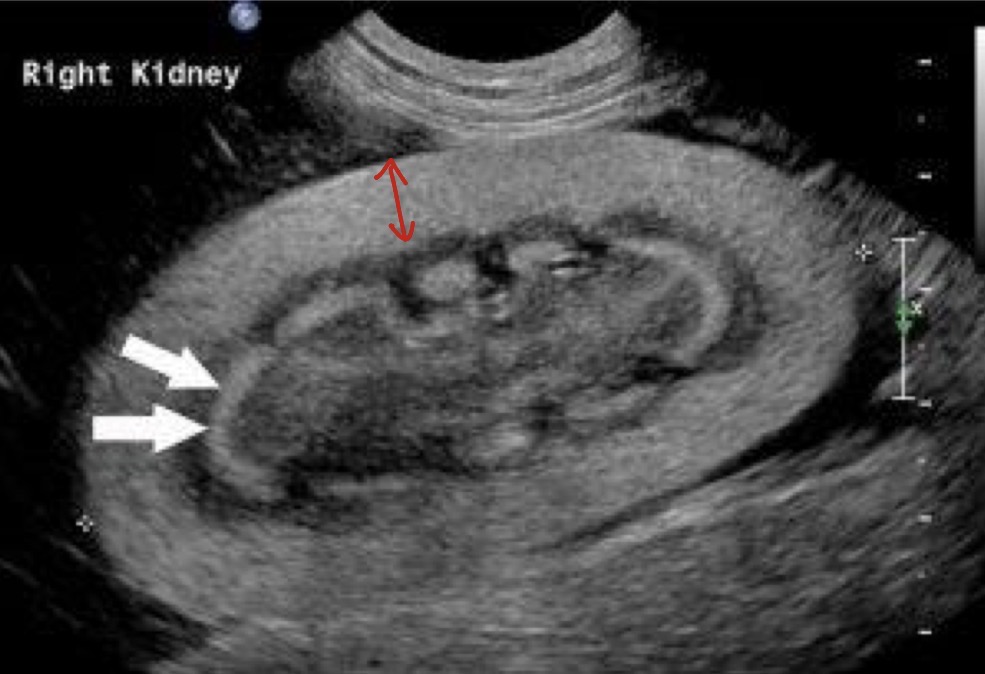

Polycystic kidney disease

What is occurring in this patient?

Hydronephrosis

What is this arrow pointing to?